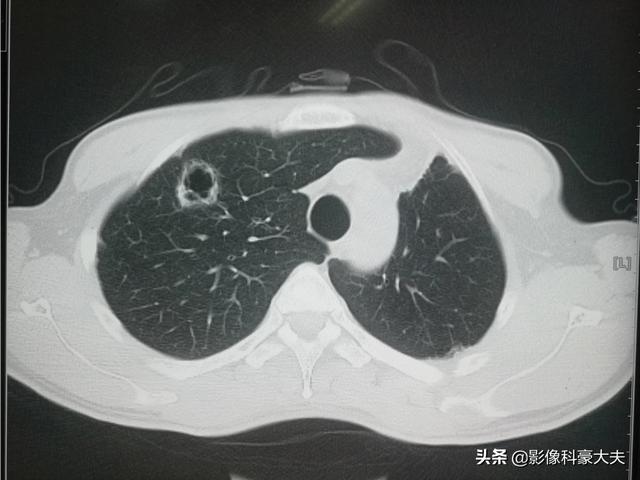

このタイプの乏血転移を治療する方法がある!プローブを腫瘍に挿入し、瞬間的に高周波高温アブレーション療法でがん細胞を焼灼する:

もう6年になるが、患者はまだ生きている。